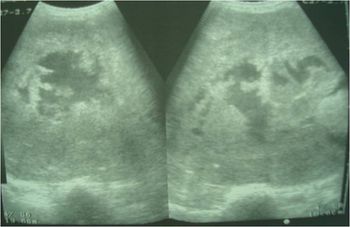

Clinical History: A 47-year-old female patient complaining from tender mass in upper outer left breast. Clinically cord-like structures were palpable in the upper outer quadrant of her left breast.